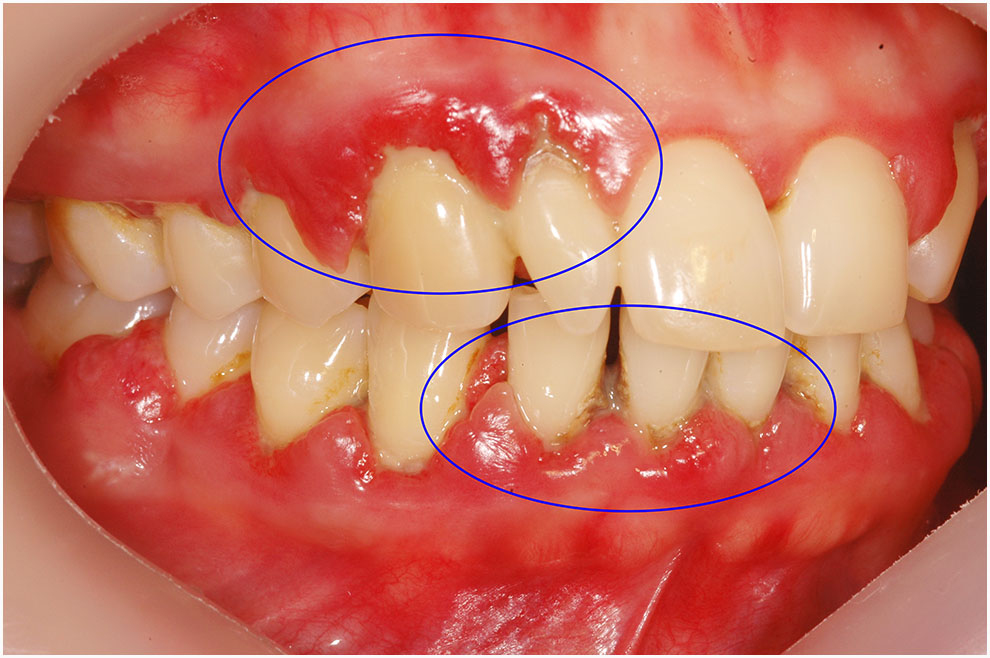

한 가지 건대치과 예시 사진입니다.

위는 치주질환이 악화한 사진이고 밑에는 건강한 상태의 치주 사진입니다.

건강한 잇몸이라면 치아를 감싸면서 치아 사이 잇몸이 뾰족하고 분홍색을 띱니다.

그런데 치주질환 발생 시 색상이 어둡게 변하거나 너무 진하게 변하며, 잇몸뼈 소실로 인하여 치아 사이 구멍이 발생하기도 합니다.

이것을 블랙트라이앵글이라 칭합니다.

밖에서 보면 뾰족했던 잇몸 끝이 동글동글해지면서 색도 빨개지게 됩니다.

가벼운 칫솔질조차도 출혈로 이어질 수 있는데요.